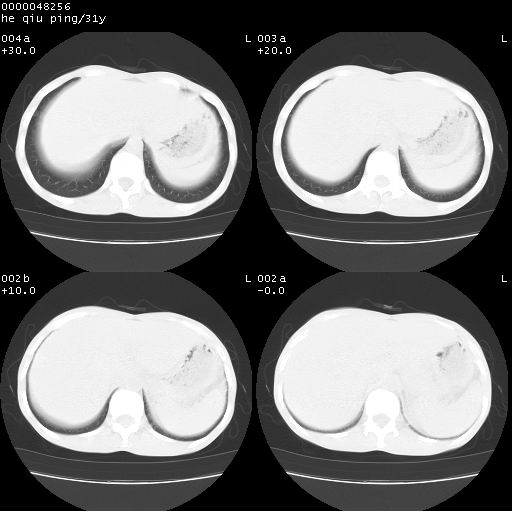

双上肺多发空洞,双飞散在分布大小不一的片状结高密度影节状大片状高密度影。符合结合肉芽肿形成及空洞形成。

双侧弥漫性病变,双上叶尖后段、下叶北段见多个空洞,多见于结核感染。右中叶及双下叶斑片状,结节状影,考虑为肉芽肿形成及支气管播散。但由于患者消瘦体质,抵抗力低下,若继发感染,如金葡菌肺炎也有可能。